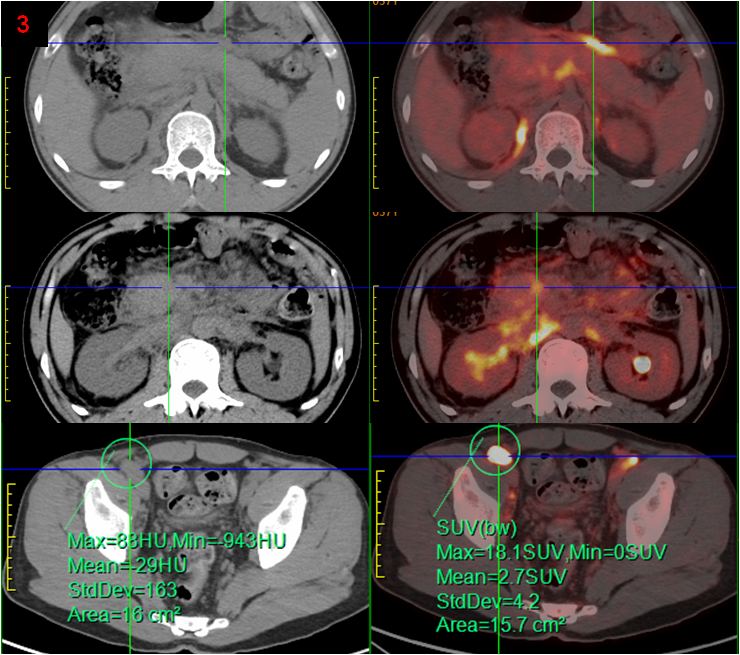

完善PET/CT檢查,示頸胸腹盆多處淋巴結或軟組織、右側腎上腺、腹膜(圖3),以及全身多處骨骼/骨髓(圖4)異常代謝,考慮淋巴瘤,建議病理檢查。

PET/CT顯示除腹膜后病變外,頸胸腹盆部存在多發(fā)高代謝淋巴結,以及多處骨骼/骨髓代謝異常,同時胰腺并未表現(xiàn)出異常高代謝,最后綜合考慮為淋巴瘤,并得到病理證實。